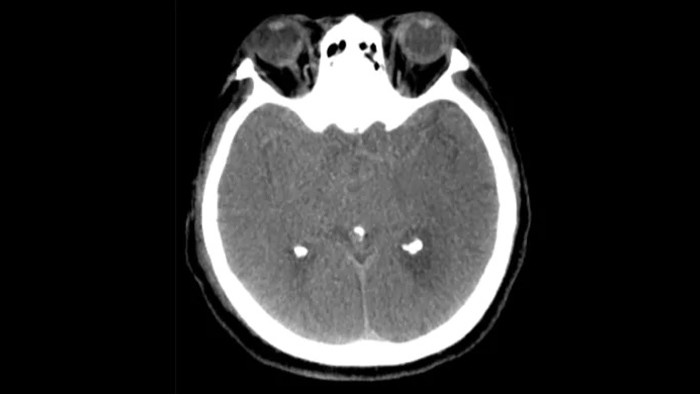

Tres SmartCT

Visualización similar a una TC

SmartCT Soft Tissue  genera una visualización de los tejidos blandos similar a la de una TC y apoya el diagnóstico del accidente cerebrovascular de tres maneras. Una exploración sin contraste ayuda a detectar los cambios isquémicos tempranos. Una exploración de fase temprana ayuda a identificar la oclusión proximal. Una exploración con contraste de fase tardía ayuda a detectar colaterales.

Ver llenado colateral

Visualización del llenado colateral

La vista dual para ver los volúmenes de TC de haz cónico de fase temprana y tardía uno al lado del otro mejora la identificación de la penumbra y permite la visualización del relleno colateral.